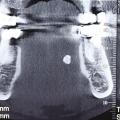

Le panoramique dentaire

Il retrouve une image ovalaire radio-opaque le plus souvent en regard de l’encoche pré-angulaire de la mandibule. Il permet d’éliminer un potentiel diagnostic différentiel non lithiasique, principalement dentaire (fig. 8). C’est un examen de débrouillage qui reste systématique, notamment pour éliminer une autre pathologie, dentaire, par exemple.

Le scanner

C’est un examen clé, de grande sensibilité et valeur localisatrice. C’est l’examen de choix. Il est le plus souvent effectué sans injection de produit de contraste. L’injection ne sera nécessaire qu’en cas de suspicion d’infection ou de tumeur (fig. 9).